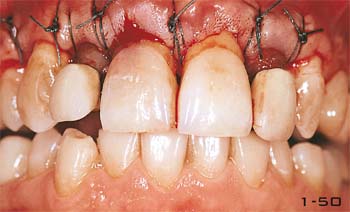

Abb. 1-49 Chirurgische Kronenverlängerung an den oberen Frontzähnen.

Abb. 1-50 Die neue Position der Gingiva und des Knochenkammes unmittelbar nach der Knochenresektion.